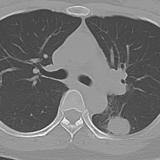

adenoca - LLL sup segm

cause of dense left hilum